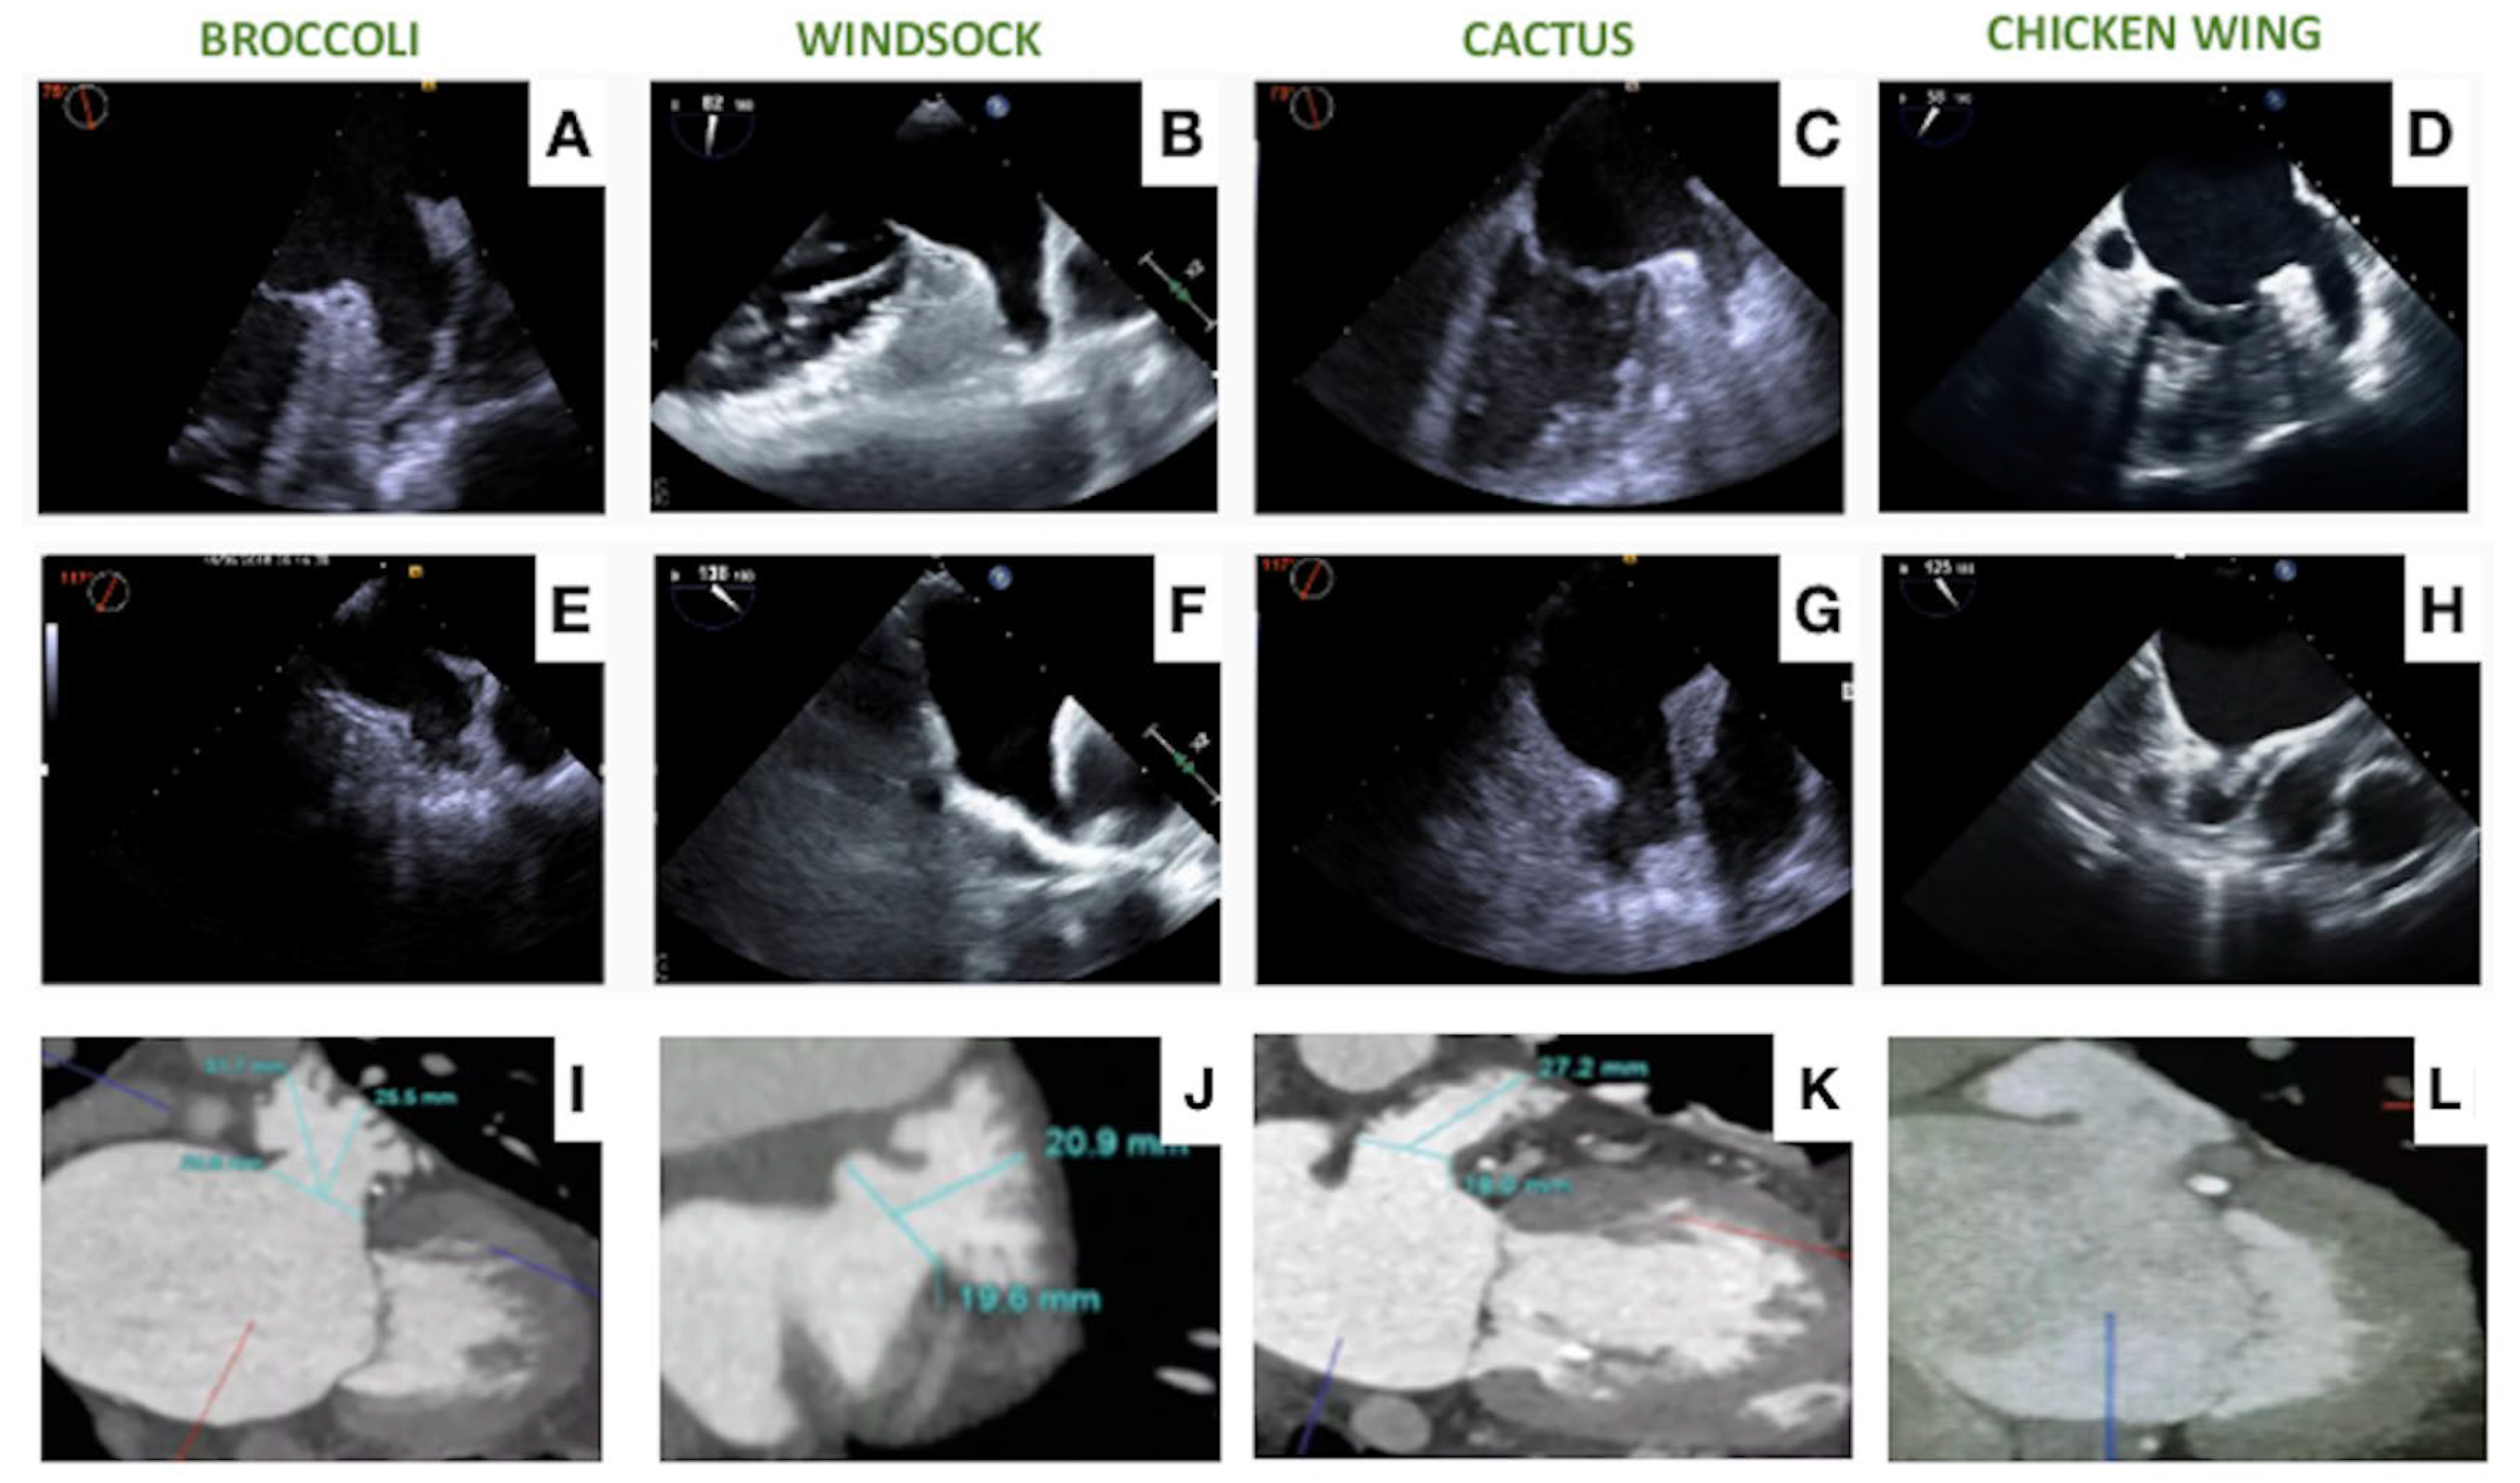

2. Contemporary Devices

2.1. The Watchman Device

2.2. Amplatzer Devices

2.3. Ultraseal Device

2.4. OMEGA Device

2.5. Lambre Device

2.6. CLAAS Device

2.7. New Devices